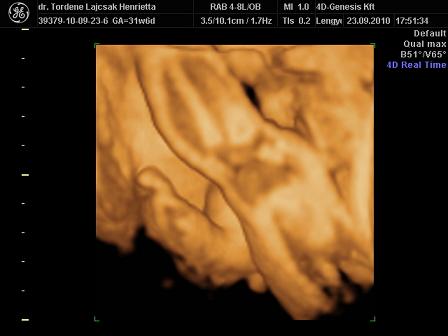

tegnap voltunk Uh-n. minden rendben van vele, egyre nagyobb. :)

méreteink:

BPD: 79,7 mm

HC: 292,5 mm

AC: 268,5 mm

FL: 57,8 mm (ezt nem tudta pontosan lemérni, mert érdekesen pózolt )

súly: 1700 g. (netes kalkulátor alapján 1750)

rakok róla néhány képet. :oops: és már 32 hetesek vagyunk...lassan finish.. :)